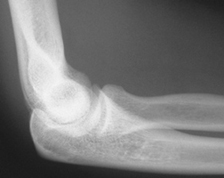

An X-ray is necessary to determine if there is a bone injury. X-rays can also help show the direction of the dislocation.

X-rays are the best way to confirm that the elbow is dislocated. If bone detail is difficult to identify on an X-ray, a computed tomography (CT) scan may be done. If it is important to evaluate the ligaments, a magnetic resonance image (MRI) can be helpful.

Normal alignment after the elbow has been reduced.

The normal alignment of the elbow can usually be restored in an emergency department at the hospital. Before this is done, sedatives and pain medications usually will be given. The act of restoring alignment to the elbow is called a reduction maneuver. It is done gently and slowly. Two people are usually required to perform this maneuver.